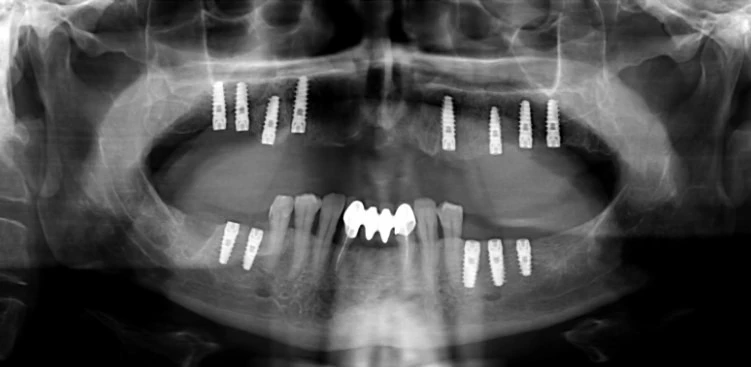

Имплант, установленный в костную ткань, берёт на себя функцию природного корня зуба. Он передаёт жевательную нагрузку на кость, стимулирует естественные процессы обновления, препятствует её рассасыванию. За счёт этого удаётся сохранить высоту и плотность костной ткани, избежать деформаций лица и поддержать здоровье соседних зубов.

Для жителей Алматы, где активный образ жизни и высокие требования к внешнему виду являются важными факторами, имплантация становится не только способом восстановить утраченные зубы, но и профилактикой возрастных изменений. Современные имплантационные системы позволяют добиться максимальной биосовместимости, исключают развитие воспаления и обеспечивают стабильный результат на долгие годы.

Эффективность имплантации подтверждается многолетними наблюдениями и отзывами пациентов. В Алматы высокий спрос на процедуру объясняется её универсальностью: импланты могут быть установлены как при одиночных, так и при множественных дефектах зубного ряда, обеспечивая полный функционал даже в самых сложных клинических ситуациях.

Утрата даже одного зуба приводит к необратимым изменениям в костной ткани челюсти. Этот процесс, известный как атрофия, развивается из-за отсутствия нормальной нагрузки на участок, где раньше находился зуб. Для пациентов из Алматы своевременное проведение имплантации позволяет минимизировать риски, связанные с изменением структуры челюстной кости, и сохранить не только внешний облик, но и здоровье всего организма.

В здоровом состоянии костная ткань поддерживает и фиксирует зубы, обеспечивая их устойчивость и правильную работу челюсти. После удаления зуба нагрузка на участок уходит, кость начинает истончаться, снижается её плотность и объём. Это не только осложняет последующую установку импланта, но и приводит к деформации лицевого скелета: впалые щеки, опущение уголков рта, появление морщин. Изменяется овал лица, что особо заметно у людей с худощавым телосложением и у пациентов среднего возраста.

С точки зрения медицины атрофия костной ткани увеличивает риск расшатывания и потери соседних зубов. Кроме того, ухудшается фиксация зубных протезов, снижается качество жевания, что влечёт за собой проблемы с пищеварением. В Алматы отмечается тенденция к обращению за стоматологической помощью уже на поздних стадиях, когда восстановление объёма костной ткани требует сложного многоэтапного лечения.